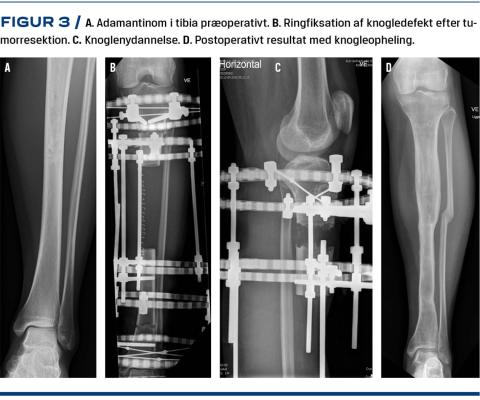

Fri fibulagraft

Den frie vaskulariserede fibulagraft (FVFG) kan som oftest anvendes ved rekonstruktion af knogledefekter efter resektion af knogletumorer i meta- og diafysen, hvor ledfunktionen kan bevares [11]. Fibulagraften udtages fra patientens egen underekstremitet og flyttes til den pågældende knogledefekt, hvor den fikseres med f.eks. skinneosteosyntese, og blodforsyningen reetableres med mikrokirurgisk teknik. Graften er vaskulær og vil over år tiltage i tykkelse og størrelse ved belastning. For at give rekonstruktionen ekstra styrke kan der anvendes en dobbeltløbet fibulagraft på underekstremiteten [12, 13] (Figur 2).

Man har i flere studier [11, 12, 14-16] undersøgt det funktionelle resultat efter rekonstruktion med FVFG og fundet et tilfredsstillende resultat med en gennemsnitlig MSTS-score på 21-29. Variationen skyldes formentlig, at der er tale om forskellige tumorlokalisationer, varierende antal patienter i studierne og forskellige typer rekonstruktion med FVFG.

I studierne har man påvist flere postoperative komplikationer, hvor størstedelen var relateret til pseudoartrose og stressfrakturer på fibulagraften. Der var desuden flere komplikationer ved donorstedet, herunder valgusfejlstilling af ankelleddet pga. utilstrækkelig stabilisering af den resterende del af fibula [17]. Endelig har man set stressfrakturer af tibia og muskelkontrakturer i crusmuskulaturen.

I de fem studier [11, 12, 14-16] blev der i alt beskrevet 62 patienter, hvoraf 14 efterfølgende blev behandlet for benlængdeforskel med bl.a. epifysiodese (lukning af vækstzone) eller forkortende osteotomi af det modsatte ben.